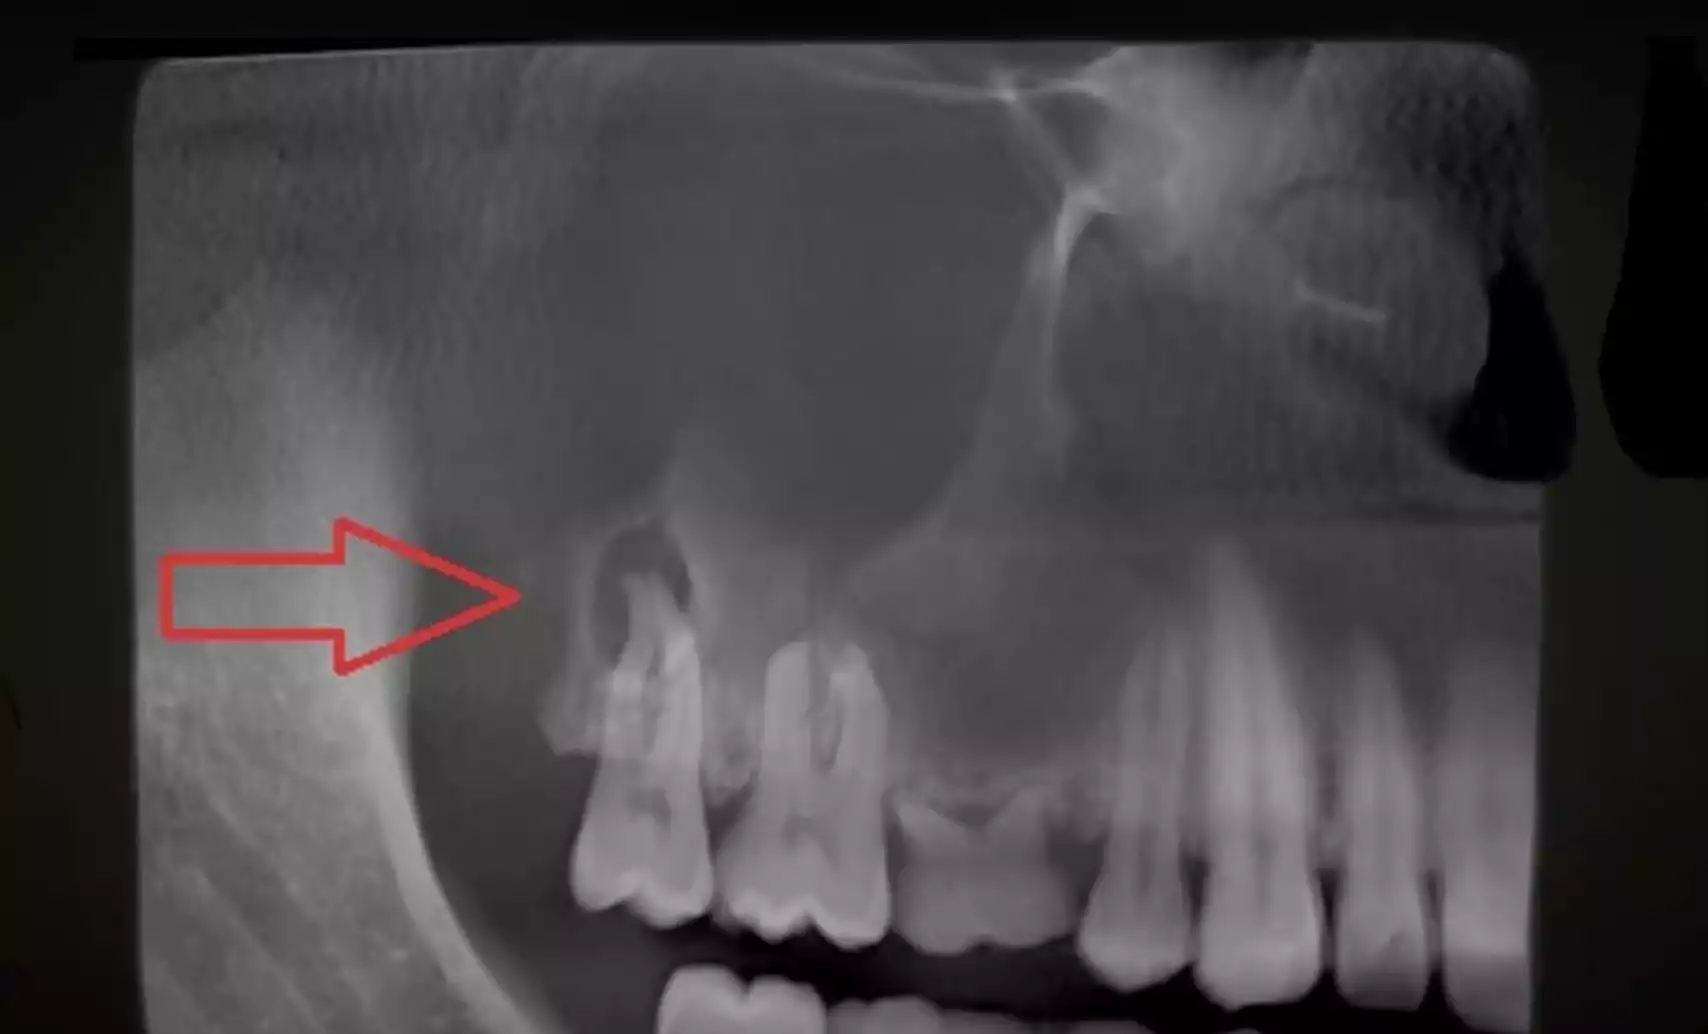

Une gingivite ou une parodontite peut devenir une porte d’entrée pour des bactéries pathogènes, impactant votre santé générale (inflammation chronique, maladies cardiovasculaires, etc.).